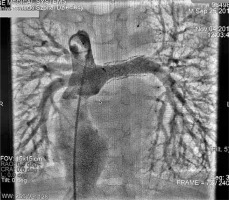

Cardiac catheterisation revealed a significant collateral vessel from the left inferior thyroid artery supplying the left lung and additional collateral vessels arising from the left (LIMA) and right (RIMA) internal mammary arteries supplying both lungs (Figure 1). The Fontan tunnel measured 14.1 mm at its junction with the IVC, widening centrally to 26 mm, and tapering to 10.9 mm at the junction with the pulmonary arteries. No fenestration was identified. The stent in the left pulmonary artery measured 9.8 mm proximally, increasing to 11.2 mm distally (Figure 2). During the procedure, an Amplatzer Vascular Plug successfully occluded the collateral vessel from the left inferior thyroid artery to the left lung, and vascular coils were placed in the RIMA and LIMA. Additionally, a 6-mm Valeo stent was implanted to create a new fenestration (Figure 3).

Figure 2

Angiography of the pulmonary arteries and Fontan tunnel. The tunnel measured 14.1 mm at its junction with the inferior cava vein, widened centrally to 26 mm and tapered to 10.9 mm at the junction with the pulmonary arteries. No fenestration was identified. The stent in the left pulmonary artery measured 9.8 mm proximally, increasing to 11.2 mm distally